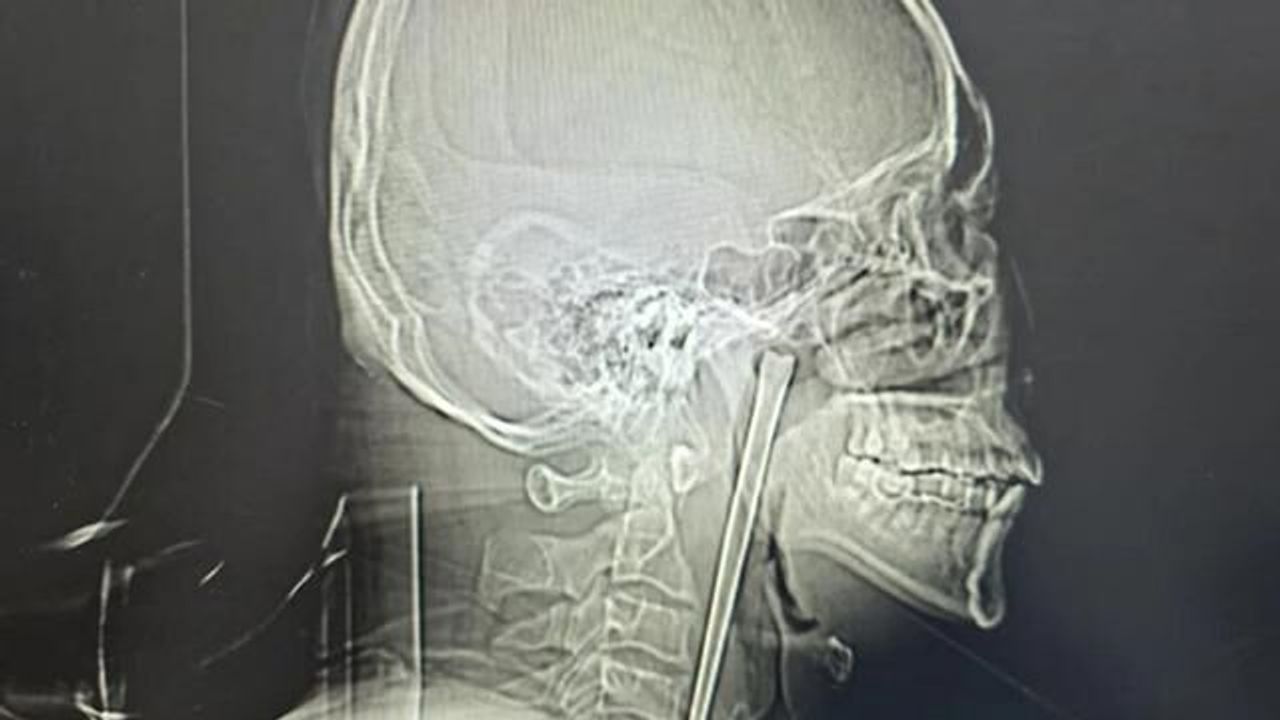

Zaman zaman boğazında hafif rahatsızlıklar yaşayan Wang, son dönemde artan şiddetli ağrılar nedeniyle Dalian Üniversitesi Teknoloji Hastanesi Kulak Burun Boğaz bölümüne başvurdu. Yapılan röntgen incelemesinde, boğazında yerleşmiş 12 santimetrelik metal çubuğun varlığı ortaya çıktı.

Dr. Huang Weipeng liderliğindeki sağlık ekibi, minimal invaziv cerrahi yöntemiyle ağız içinden yapılan hassas bir müdahaleyle çubuğu çevre dokulara zarar vermeden çıkardı. Ameliyat sonrası Wang'ın ağrıları ve ödemi tamamen geçti. Hastane yetkilileri, bu vakayla ilgili kamuoyunu bilinçlendirmek için uyarılarda bulundu.